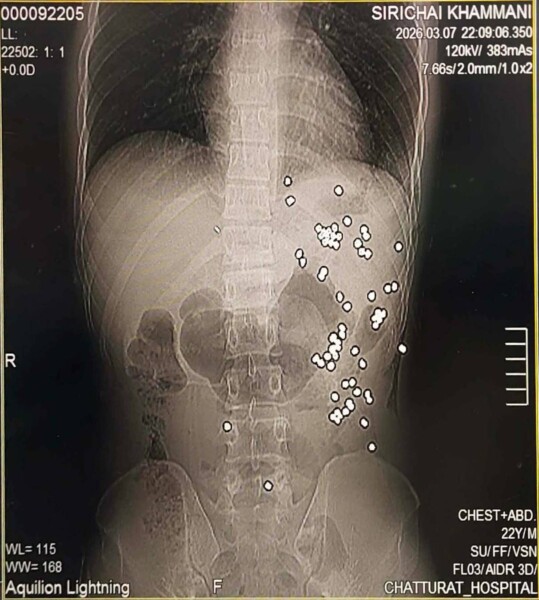

จำนวน3รายอีก 3ราย อยู่ระหว่างสอบสวนขณะที่คนเจ็บยังสาหัสลูกตะกั่วฝังใน 67 เม็ด นอกจากนี้คนเจ็บยังเป็นนักฟุตบอลเดินสายอีกด้วย เปิดกล้องเกิดเหตุวัยรุ่นยิงกันเมื่อ วันที่ 7 มีนาคม69 เวลา 20.42 น.ที่ผ่านมา โดยพนักงานสอบสวน สภ.จัตุรัสได้รับแจ้งจากวิทยุ191ว่ามีเหตุวัยรุ่นยิงกันที่บริเวณ หน้ารีสร์อทแห่งหนึ่งในหมู่บ้านโนนฝาย ต.หนองโดน อ.จัตุรัส จ.ชัยภูมิ มีผู้ได้รับบาดเจ็บ 1 รายสาหัส 1 ราย จึงรายงานให้ พ.ต.อ.เสกสรร บุญยรัชนิกร ผกก.สภ.จัตุรัส พร้อมประสานเจ้าหน้าตำรวจชุดสืบสวนเข้าตรวจสอบเมื่อไปที่เกิดเหตุพบว่ากลุ่มผู้ก่อเหตุได้หลบหนีไปก่อนหน้านี้แล้ว ส่วนผู้บาดเจ็บทางญาติๆได้นำส่ง รพ.จัตุรัส ทราบชื่อผู้บาดเจ็บคือ นายศิริชัย คำมณี หรือคิง อายุ 23 ปี บ้านเลขที่ 95 บ้านโนนคร้อ ต.บ้านขาม อ.จัตุรัส จ.ชัยภูมิ ซึ่งเป็นพนักงาน รางวัดที่ดิน ที่อ.จัตุรัส ซึ่งถูกยิงที่ใต้ลิ้นปี่ และถูกฟันที่แขนซ้ายบาดเจ็บสาหัส

ต่อมาวันนี้ 9 มี.ค.69 นางจิรนันท์ คำมณี อายุ 43 ปี บ้านเลขที่ 95 บ้านโนนคร้อ ฯแม่ผู้บาดเจ็บได้นำเปิดเผยต่อผู้สื่อข่าวช่วยนำเสนอข่าวให้เนื่องจากเกรงว่าจะไม่ได้รับความเป็นธรรมในเรื่องของคดี เนื่องจาก 1 ในผู้ก่อเหตุยังเป็นลูกคนมีสีอีกด้วยทั้งนี้ตนเองเกรงว่าจะมีการสลับตัวของผู้ก่อเหตุจึงได้นำเรื่องมาเปิดเผยต่อผู้สื่อข่าวดังกล่าว เนื่องจากลูกตนบาดเจ็บสาหัสทั้งถูกฟัน และ ถูกยิงกระสุนลูกปลายฝังตามตัวกว่า 67 ลูก